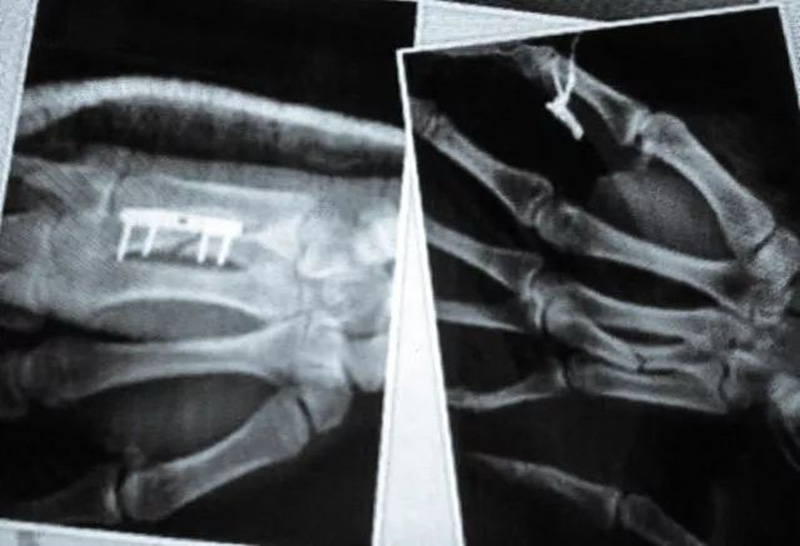

取得这些成绩的同时

他手上始终带着高二时

因掌骨骨折

而打进去的钢板和钢钉

两次大伤

两次将钢板植入身体

20岁左右的年纪